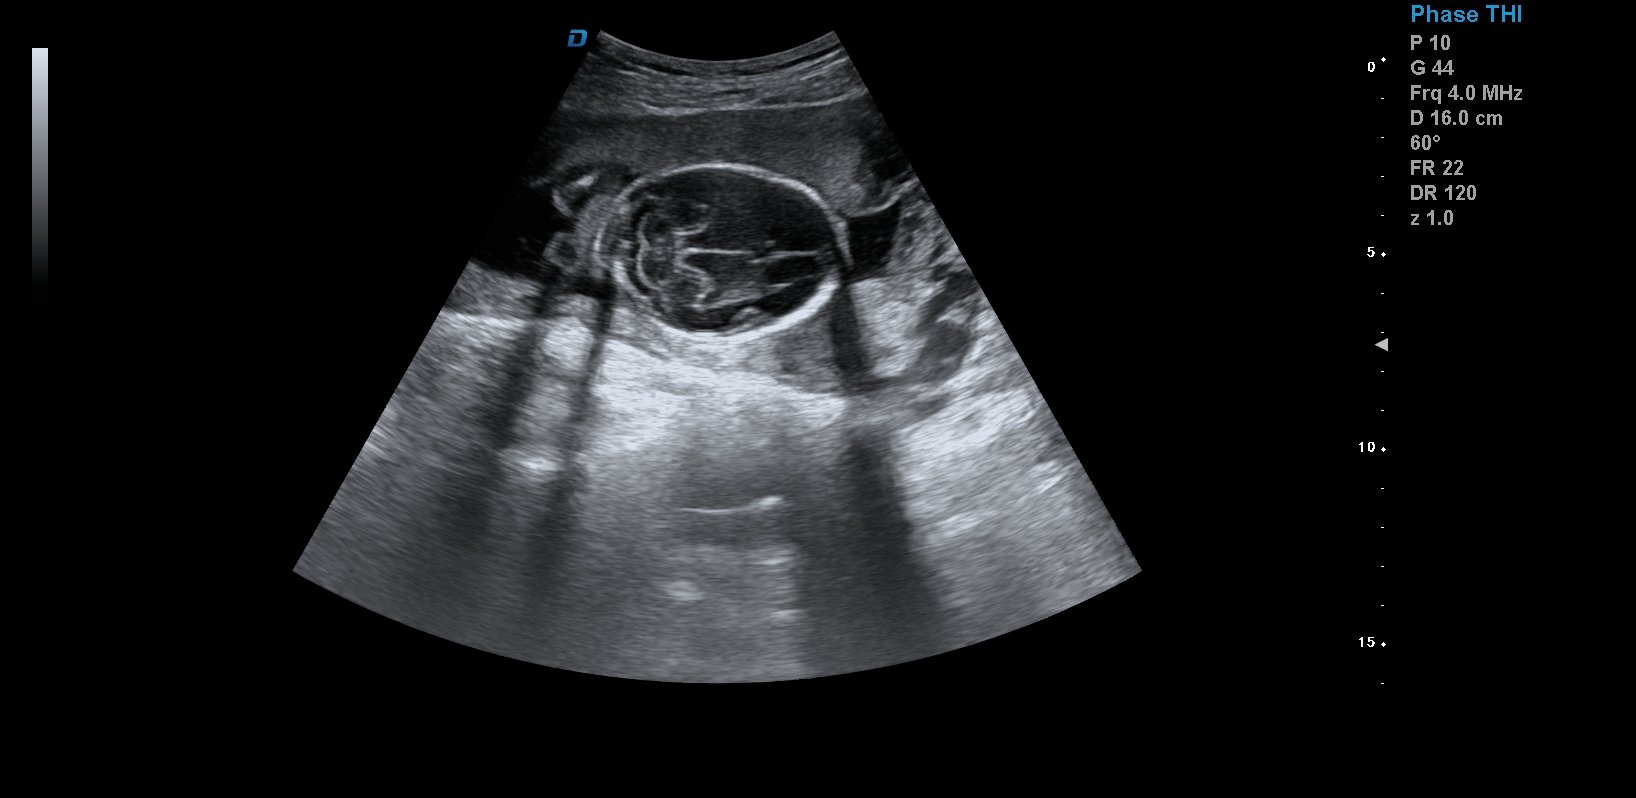

首先,四維彩超檢查是采用高清晰度的彩超儀對(duì)胎兒進(jìn)行各個(gè)心臟器官及組織的一次全面檢查,可以立體顯示胎兒的發(fā)育情況,胎兒在子宮內(nèi)的任何狀態(tài)都可以觀察到。對(duì)胎兒畸形能夠早診斷,及時(shí)地做出相應(yīng)的措施,以達(dá)到優(yōu)生優(yōu)育的標(biāo)準(zhǔn)。

四維彩超不但成像清晰,更是在三維的基礎(chǔ)之上附加時(shí)間這個(gè)矢量。這就在排畸的同時(shí)能時(shí)刻觀察寶寶在宮內(nèi)的一舉一動(dòng),吃手指、打哈欠、吮吸……寶寶在宮內(nèi)憨態(tài)可掬,讓孕媽媽母愛(ài)井噴,幸福不已。這也是孕媽媽們選擇四維的主要原因,試想,誰(shuí)不想在辛苦懷孕期間提前看一看自己寶寶的模樣呢?

1、四維彩超是目前先進(jìn)的彩色超聲技術(shù).能直觀立體現(xiàn)實(shí)人體器官動(dòng)靜態(tài)三維結(jié)構(gòu),一定程度上提高臨床診斷的準(zhǔn)確性。

3、清晰成像:采用先進(jìn)的超聲成像技術(shù),擁有高清晰,高分辨率、高精確度優(yōu)點(diǎn),能清晰看到包括生殖器、內(nèi)臟器官在內(nèi)的胎兒的各個(gè)部位發(fā)育情況.

四維彩超最佳時(shí)間是24-26周。這個(gè)時(shí)候胎兒結(jié)構(gòu)發(fā)育完善,可觀察到大多數(shù)的胎兒畸形。胎兒30周左右最好再去做一次四維彩超,因?yàn)樘航Y(jié)構(gòu)是一個(gè)逐漸發(fā)育的過(guò)程,畸形沒(méi)有發(fā)展到一定程度可能不能被檢查到。